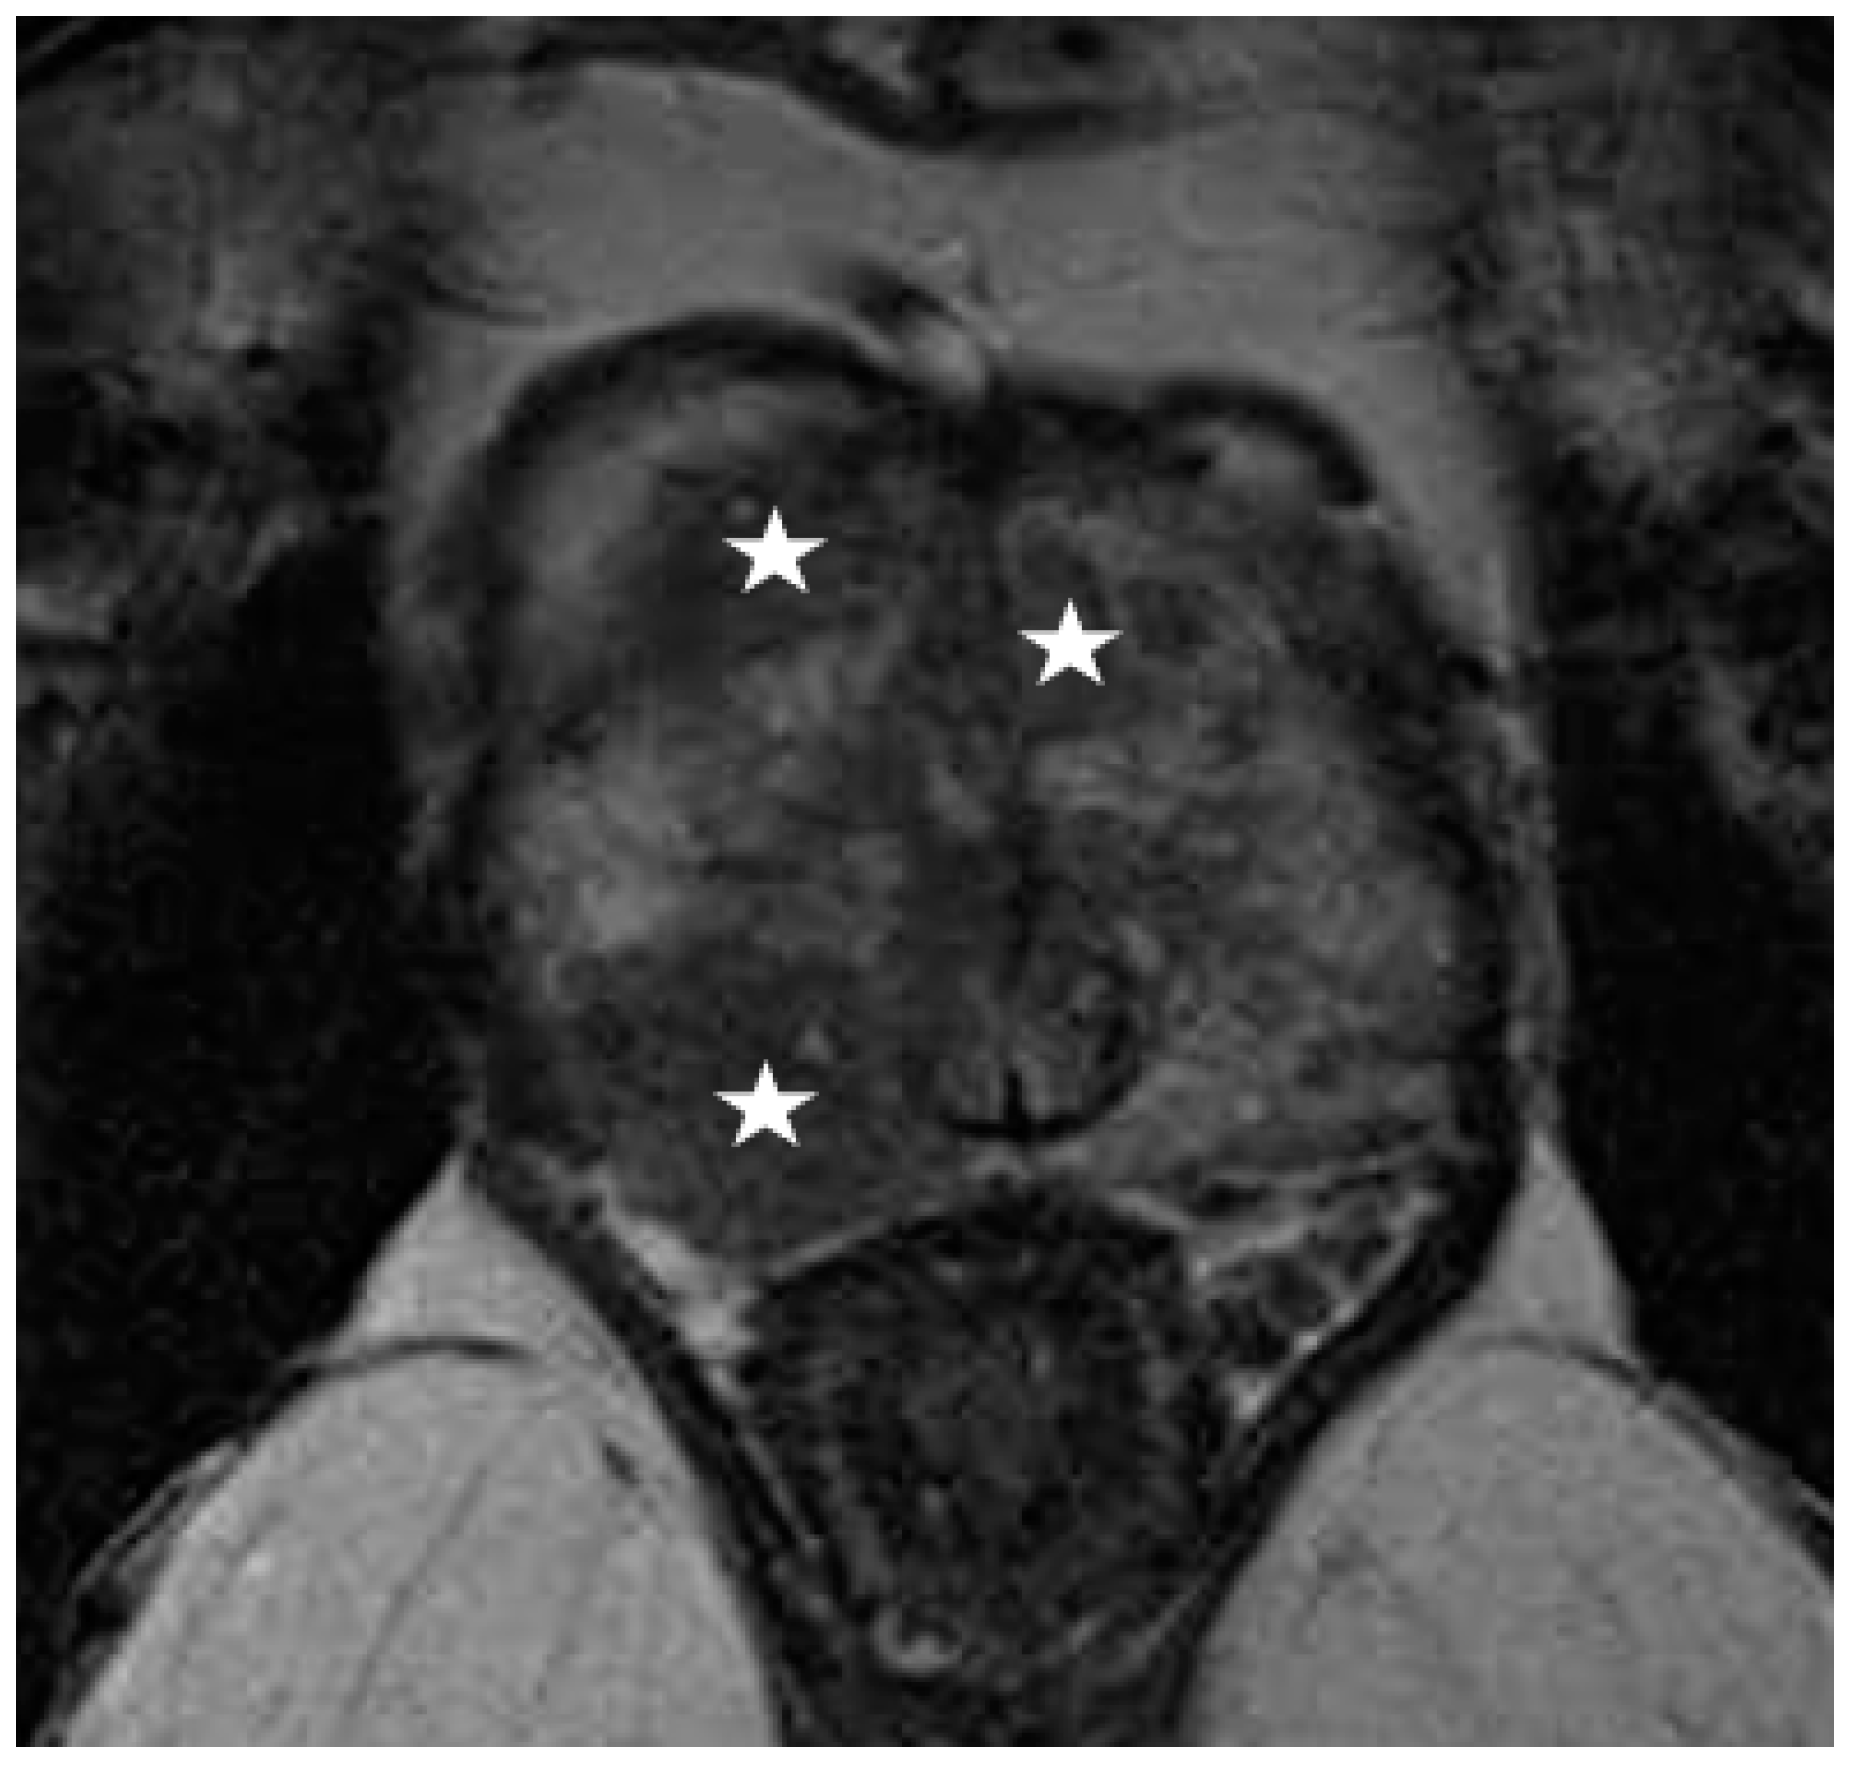

Recently, several studies have compared different deep CNN models on zonal segmentation. Cuocolo et al. [48] compared three deep learning methods, UNet, an efficient neural network (ENet) [60], and efficiently residually factorize ConvNet (ERFNet) [61] in the PROSTATEx public dataset. ENet (0.91, 0.87, 0.71) and UNet (0.88, 0.86, 0.70) were more accurate than ERFNet (0.87, 0.84, 0.65) in terms of DSC (for WG, TZ and PZ, respectively), while ENet outstood the other two methods, with faster convergence speed and fewer parameters. Saunders et al. [49] compared the performance of independent training, transfer learning, and aggregated learning based on 3D and 2D U-Net models, on the premise of limited training data. In addition, 3D U-Net was found to be more robust to a small sample size (five training cases) than 2D U-Net by an average DSC of 0.18, while transfer learning and aggregated learning (similar DSC: 0.73, 0.83, 0.88 for PZ, CG, WG, respectively) both outperformed independent training (DSC 0.65, 0.77, 0.83) when using five internal training cases. Predictably, automated segmentation between PZ and TZ can become challenging in cases where tumours span across both zones, since false positives like prostatitis in the PZ reduce its normal high T2 signal to become isointense to the TZ, whereas severe benign prostatic hypertrophy in the TZ compresses the PZ, reducing the ability to discriminate between the two zones (Figure 2, Figure 3 and Figure 4).

Figure 2.

Multifocal prostate cancer seen as hypointense lesions on T2-weighted imaging (star), obscuring the boundaries between peripheral and transition zone, making zonal segmentation challenging.